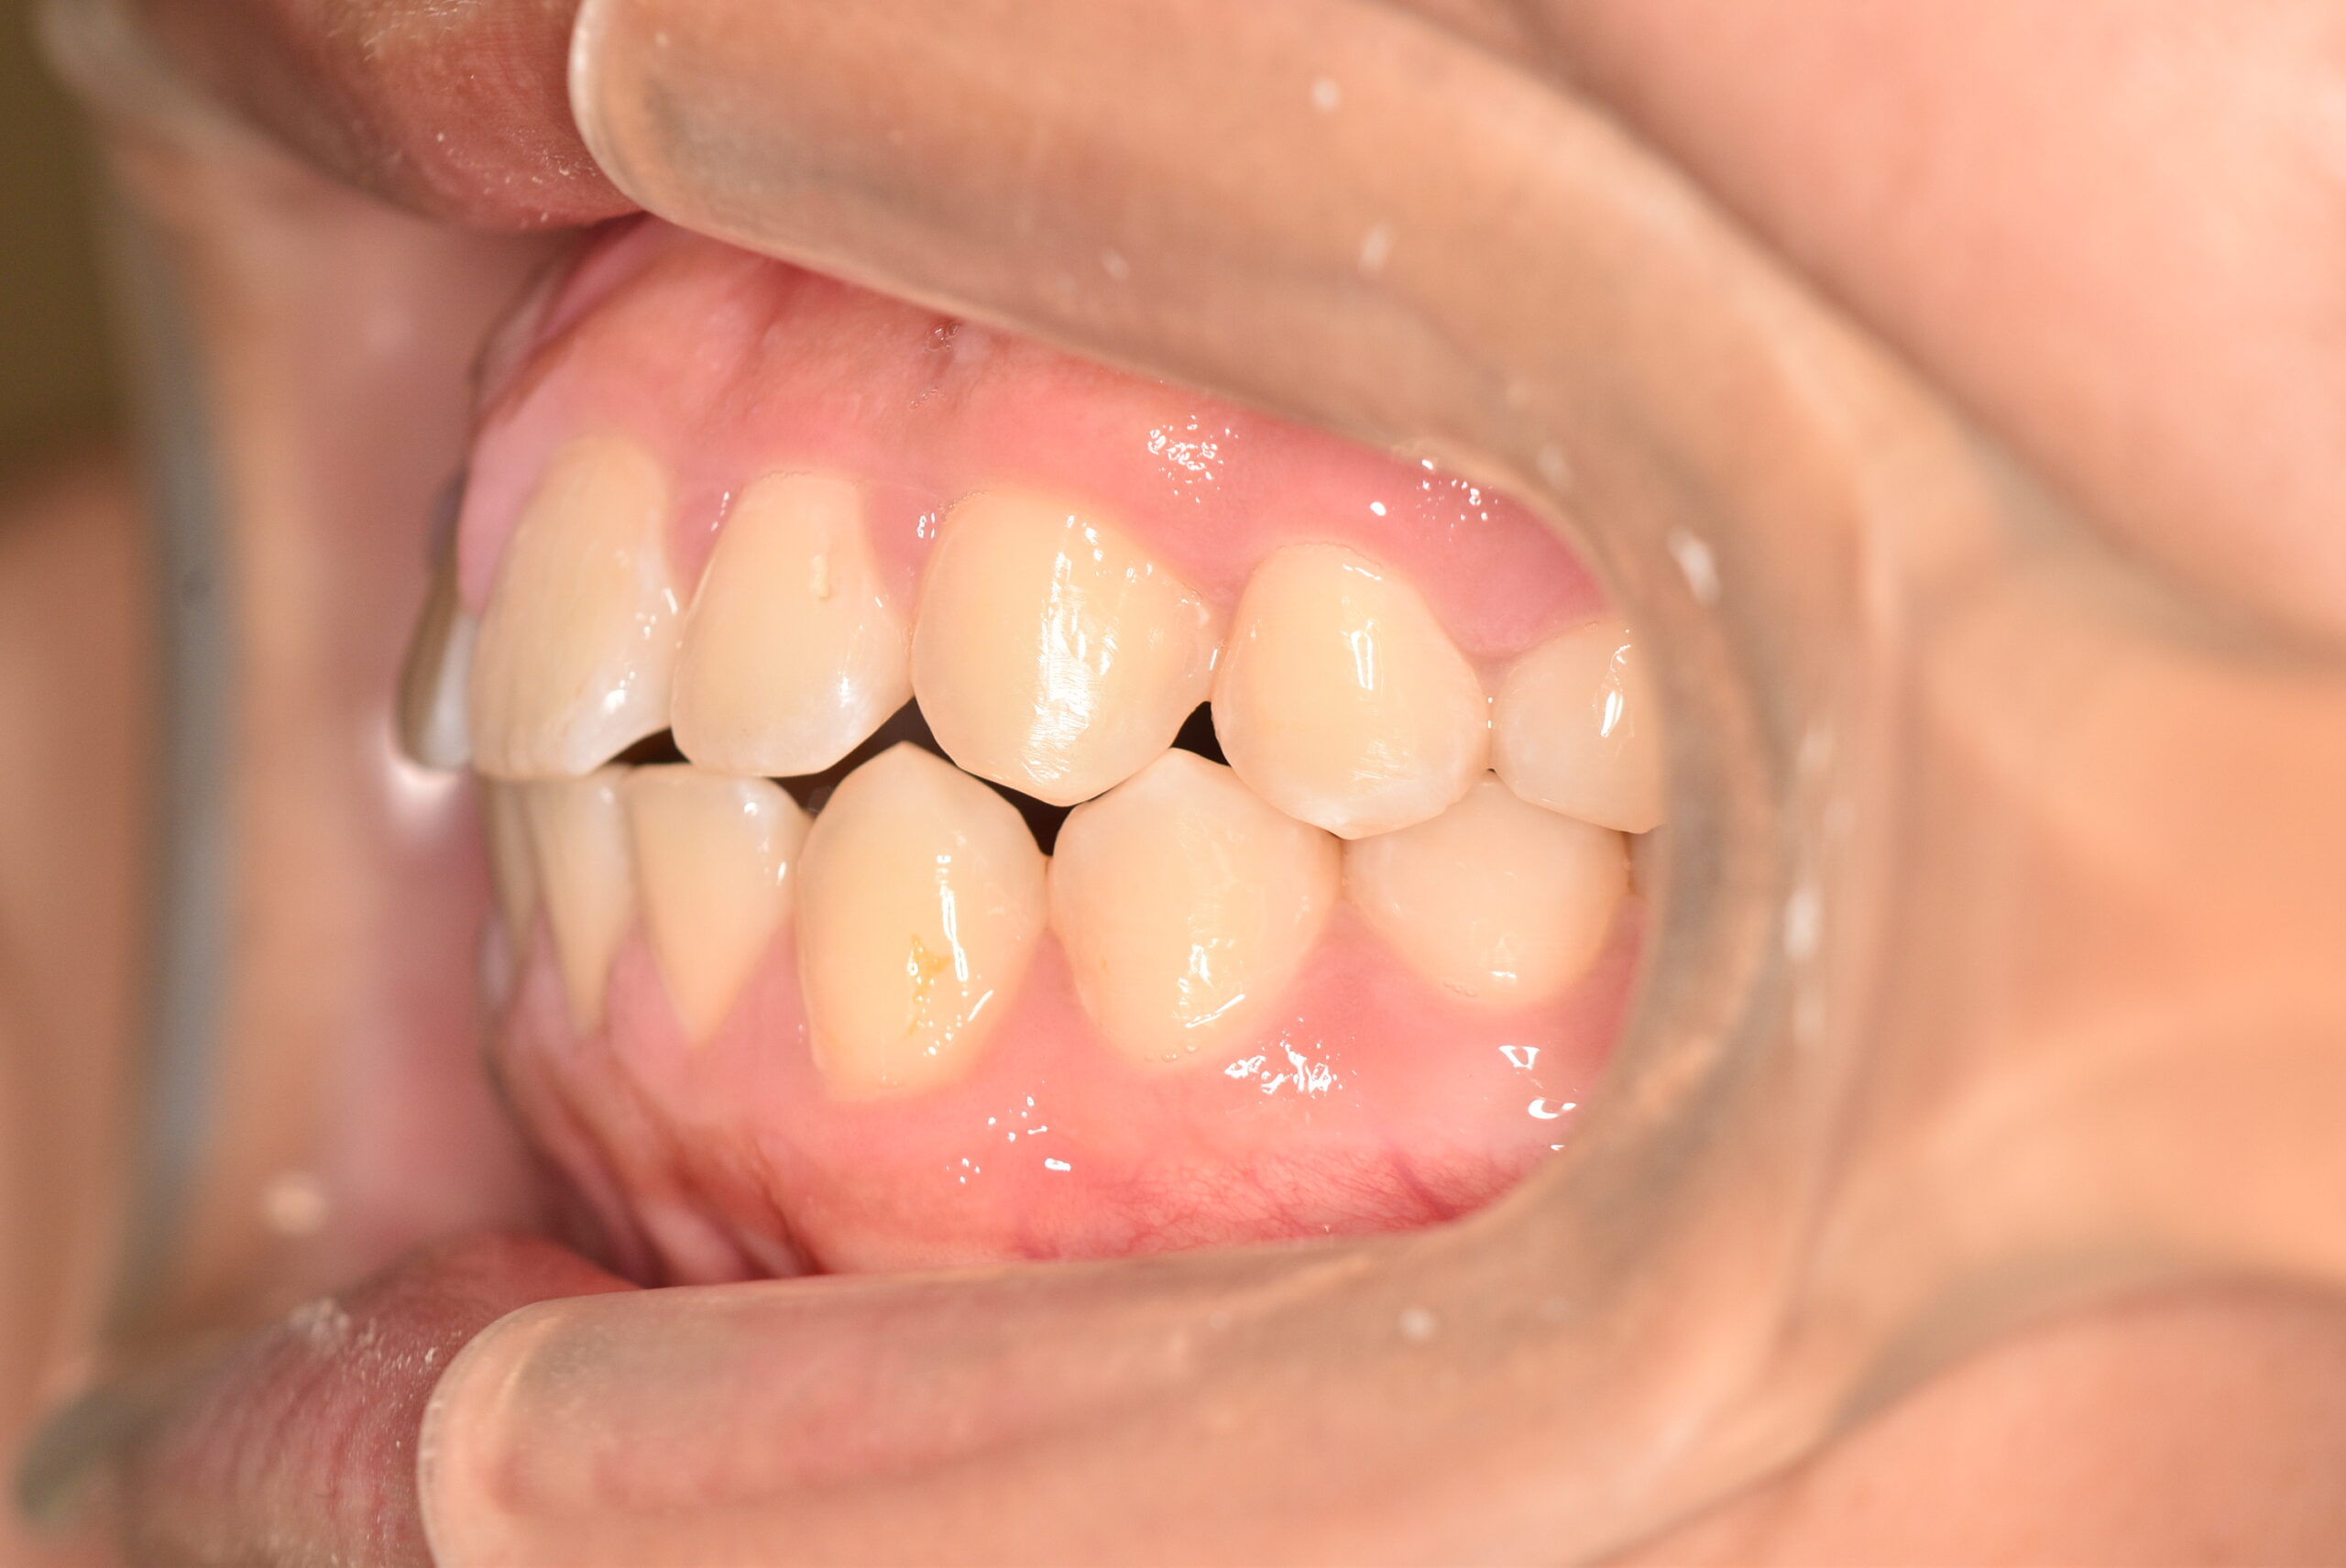

初診時

症例 症例 症例 症例

検査の結果、過蓋咬合、上顎前突を伴うアングルⅡ級1類不正咬合と診断しました。

治療としては、初期段階の治療として、機能的矯正装置で鼻呼吸の獲得と舌の位置や口唇の閉鎖といった筋機能習癖の改善を行いました。